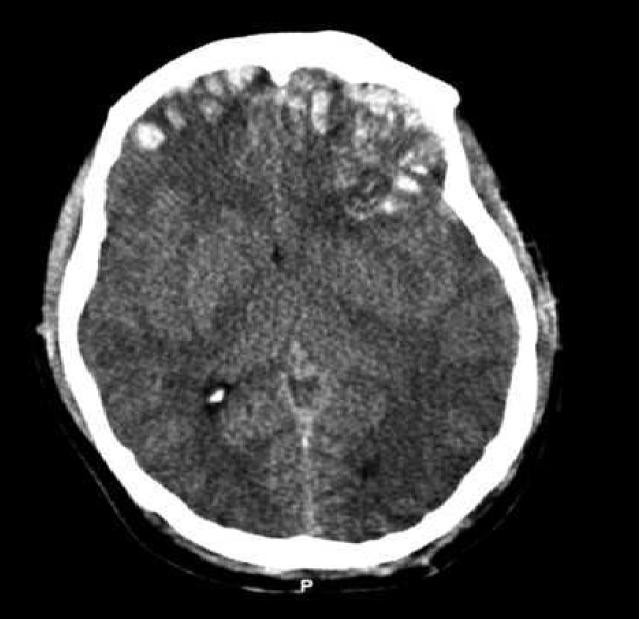

КТ-картина диффузного аксонального поражения мозга характеризуется увеличением объема мозга, в результате которого под сдавлением находятся боковые и III желудочки, субарахноидальные конвекситальные пространства, а также цистерны основания мозга. Нередко выявляют наличие мелкоочаговых геморрагий в белом веществе полушарий мозга, мозолистом теле, подкорковых и стволовых структурах.

- КТ головного мозга томографическая, аксильная – с контрастным усилением и без такового.

КТ помогает увидеть полную картину и определить:

- Тяжесть ушиба;

- Плотность тканей;

- Степень отечности;

- Петехиальные кровоизлияния;

- Контузионный очаг;

- Зону детрита и пр.

К примеру, ушиб средней тяжести дает томограмму очагов с пониженной плотностью, либо повышенную – при геморрагическом типе. Это позволяет определить дальнейшие действия врача.

Если же пациент поступает в больницу с тяжелой степенью ушиба, то времени на дополнительные диагностические мероприятия просто нет – надо экстренно спасать человека. Поэтому делается КТ и врач видит состояние головного мозга: очаги повышенной (сгустки крови) и пониженной (размозжения и отека) плотности. Тогда может быть назначена экстренная операция.